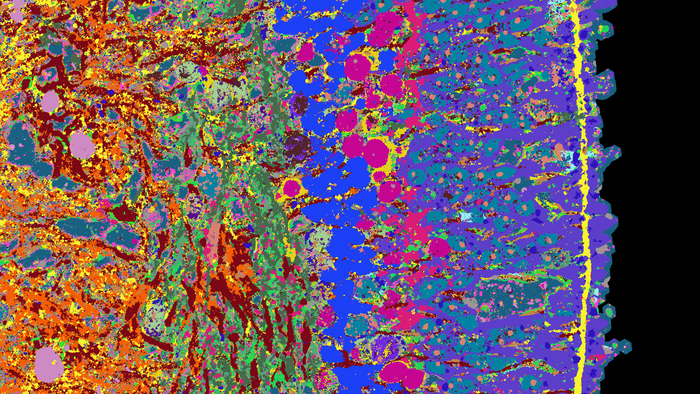

视网膜类器官横切面的细节。不同的组织结构以不同的颜色可见

通常,研究人员使用荧光显微镜来突出组织中的三种蛋白质,每种蛋白质都有不同的荧光染料。由于技术原因,一次染色不可能超过5种蛋白质。在4i技术中,使用了三种染料,但这些染料在测量后从组织样本中洗掉,并染色了三种新的蛋白质。这个步骤由机器人执行了18次,整个过程总共花费了18天。最后,计算机将这些单独的图像合并成一个显微镜图像,在这个图像上可以看到53种不同的蛋白质。它们提供了构成视网膜的单个细胞类型的功能信息;例如,杆状细胞、锥状细胞和神经节细胞。